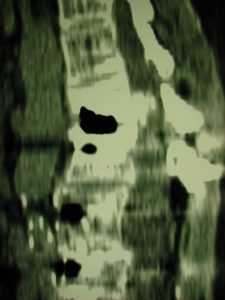

Εικόνα 14 (α,β,γ,δ,ε,ζ,,η,θ) Ο τελευταίος έλεγχος δια Αξονικής Τομογραφίας έγινε στις 30/05/2016. (α,β,γ) : Οβελιαία (Sagittal) τομή Παρατηρείται ότι παραμένει στην ίδια περίπου έκταση η βλάβη στο επίπεδο Ο1-Ο2, έχει όμως προηγηθεί εκφύλιση και σε άλλα επίπεδα (δ, ε, ζ) κυρίως στο Ο3-Ο4. (η)  Μετωπιαία (coronal) τομή (θ.)  Εγκαρσία (Axial) μεγάλη στένωση στο επίπεδο Ο1-Ο2.